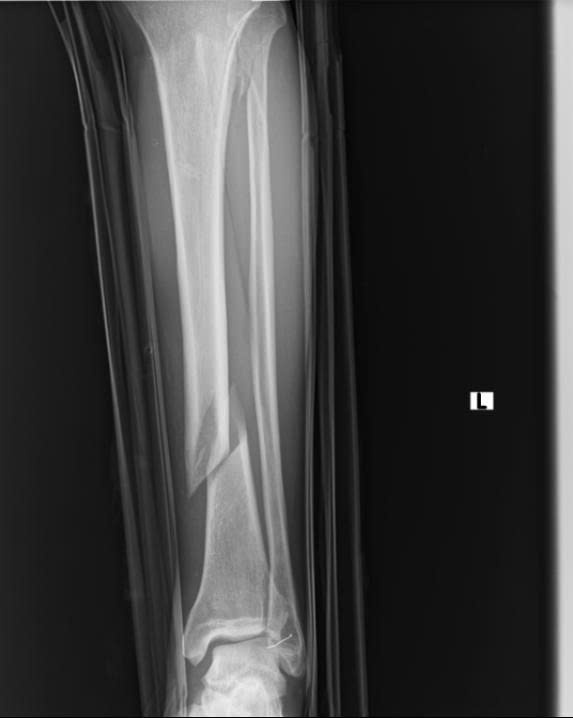

Hình ảnh: Xquang xương trước phẫu thuật

- Hình ảnh X-quang sau mổ cho thấy xương được nắn chỉnh và cố định vững chắc